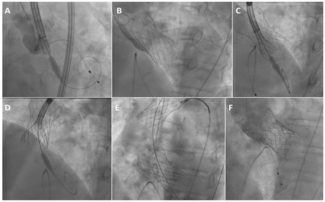

Stent delivery into tortuous or calcified coronary lesions may cause challenges during PCI. The authors offer an approach of leaving a buddy wire in a jailed position, which allows placement of multiple overlapping stents.